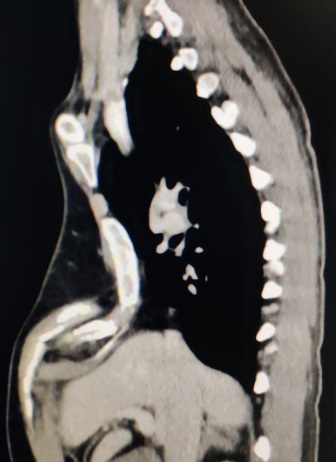

X线检查:正位片见心脏左偏,位于左侧胸腔,左侧肋骨走向异常;侧位片见前胸壁明显畸形。CT检查:前胸壁不对称、不规则型凹陷,凹陷最低处低于脊柱前沿。心脏受压,右侧胸廓严重变形(图1-2)。三维重建:前胸壁极度变形,呈不规则、不对称型凹陷。胸骨体受累,右侧胸壁结构变形严重(图4-6)。

图3,CT提示重度畸形。